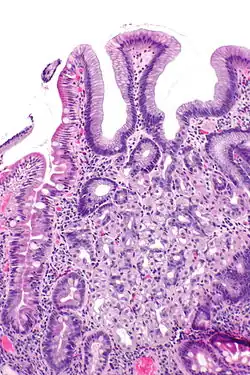

Heterotopie (z řec. heteros (odlišný, jiný) + τόπος (topos, místo)) nebo také ektopie znamená výskyt orgánu nebo tkáně na jiném místě, než je obvyklé. Příkladem heterotopie je choristie.[1]

V lékařství je to výraz pro orgány nebo zbytky tělesných orgánů, jež se vyskytují na neobvyklých místech, kde mohou být též příčinou novotvarů.

- žaludeční sliznice v Meckelově divertiklu (může v něm dojít k vzniku peptického vředu s následným krvácením)